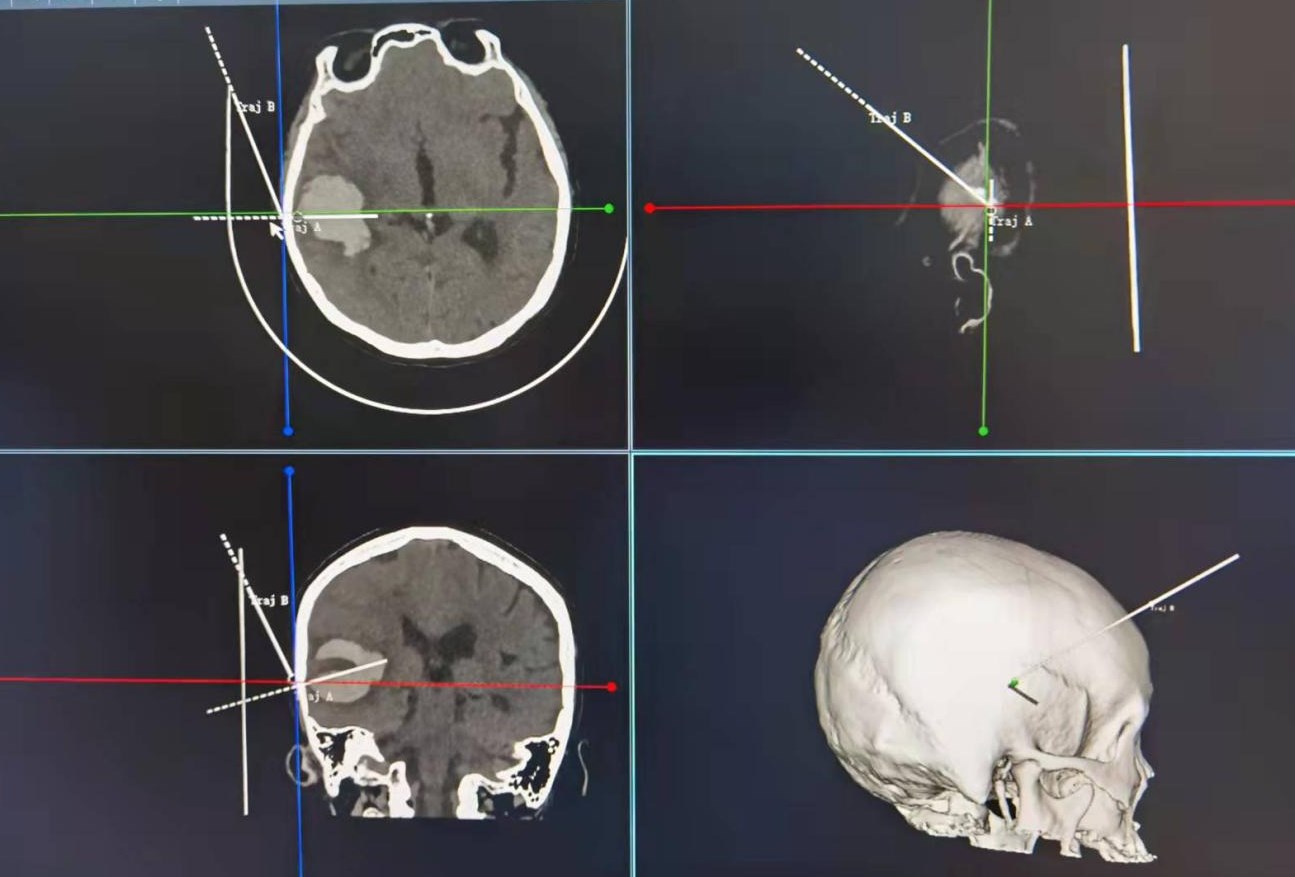

神经外科机器人手术中精准定位颅内血肿

机器人借助于影像导航系统完成手术路径的设定

患者为59岁女性,既往高血压史4年,未规律服药,平素未监测血压。此次因突发头痛、头晕伴恶心呕吐3天,加重1天入院。入院后体查,患者精神差,意识模糊,左侧肢体无力,左上肢肌力Ⅳ级,下肢Ⅴ级,右侧肢体肌力正常。头颅CT提示为右侧颞叶脑出血,出血量约30ml,占位效应明显,手术指征明确,积极术前准备,经过治疗组讨论后,在机器人借助于影像导航系统下,精准定位血肿位置,成功实施小骨窗开颅,显微镜下清除血肿。手术顺利,手术总用时1小时。术后复查头颅CT显示颅内血肿完全清除,患者意识清楚,头痛、头晕等症状较手术前明显改善,术后患者神经功能恢复良好,真正实现了微创、精准、高效。

据侯博儒介绍,高血压脑出血外科治疗的两大目的即“挽救生命和最大限度地恢复神经功能”。近些年,许多专家学者对高血压脑出血外科治疗的不断探索与研究,出现众多手术方式及手术入路,但对其最优手术方式至今尚未达成一致共识。传统外科手术通过单一的CT或MR 影像判断病灶位置,规划手术路径。这种方式存在着病灶定位难度大、无法定位重要功能组织、无法定位颅内血管从而导致手术后脑水肿加重、再出血的风险等问题。神经外科机器人借助于影像导航系统,精确定位病灶位置的同时,更加精准的规划开颅时的骨窗位置,以更小的骨窗达到更大范围的暴露。同时,机器人基于多模态影像融合技术,可以将颅内血管结构充分的展现出来,从而有效的帮助医生避开重要的血管规划穿刺路径,从而形成有针对性的、个性化的立体定向手术方案。